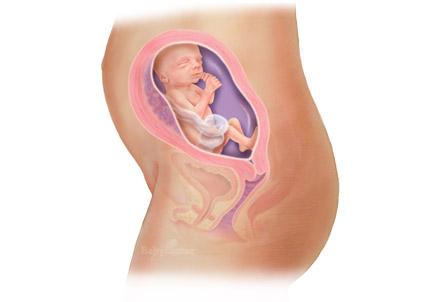

25 semanas

Como seu bebê está crescendo

Mesmo sem ar nos pulmões, seu bebê começa a fazer alguns exercícios de respiração.

Por outro lado, os cinco sentidos estão se desenvolvendo com rapidez.

Tomografias do cérebro de fetos nesta fase mostram que os bebês respondem ao toque e que, se uma luz for colocada diante da barriga das mães, eles tendem a virar a cabeça -- o que, segundo especialistas, indica o funcionamento do nervo óptico

A cada dia que passa, seu filho se parece mais com o recém-nascido que será daqui a alguns meses. O cabelo já tem cor e textura, embora depois do nascimento elas possam mudar. Bebês que nascem com cabelo escuro muitas vezes depois ficam com cabelo claro e vice-versa.

O seu bebê está mais ou menos

do tamanho de um alho-poró.